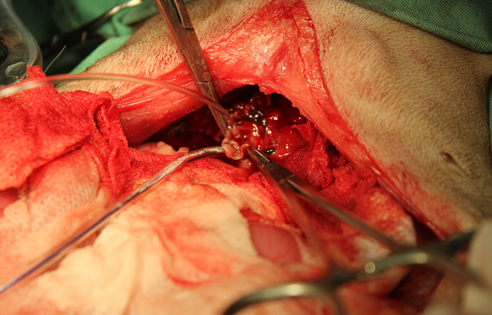

破裂した胆のうを確認しました。

胆のうを切除し、胆管内の洗浄を行いました。胆管の再疎通は問題ありませんでした。 術後は2日ほどで元気、食欲とも改善し、経過は良好です。肝臓や胆のうの病気の主な原因はやはり食事ですね。ジャーキー類などのおやつや缶詰ばかり食べているワンちゃんに多いです(t0t)みなさんのわんちゃんも食生活にはきをつけましょうね(^o^)!